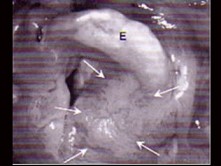

6.CT檢查見下圖,進一步的檢查是  (    )

11.MRI檢查結果如下圖,下一步最重要的檢查是  (    )